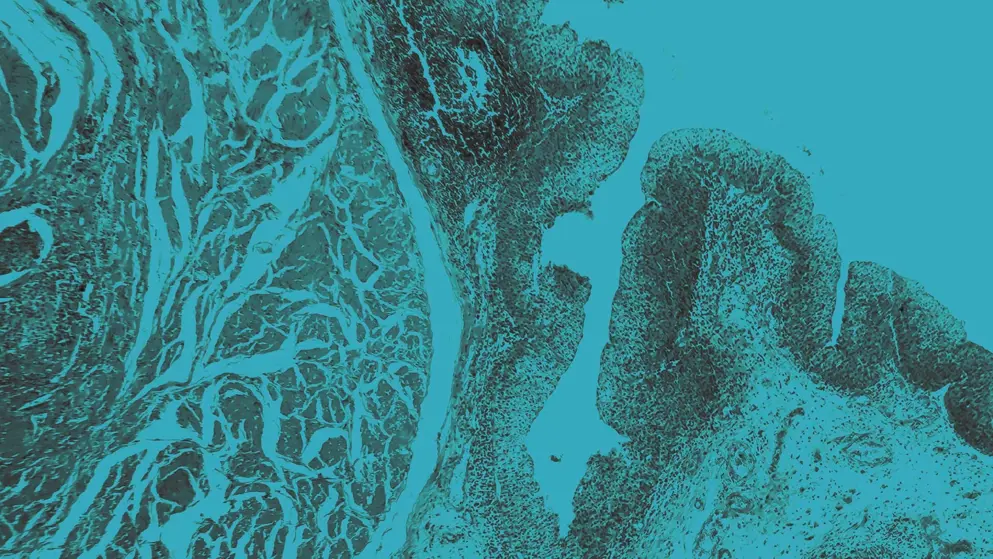

Bladder Cancer micrograph, blue overlay

Bladder cancer